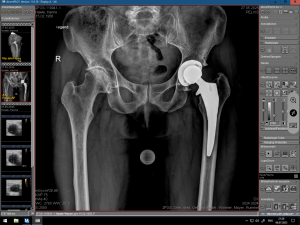

(Bilder: 1-3 Röntgenbild vor der OP mit Arthrose der linken Hüfte,

Digitale Prothesenplanung, Röntgenbild nach der OP)